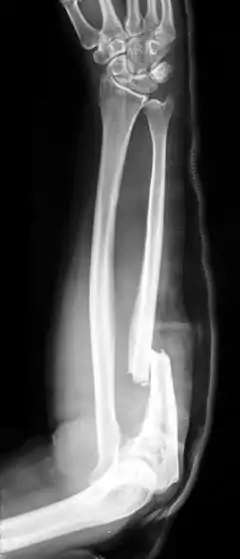

Monteggia fracture

An isolated fracture of the ulna, also called a night stick fracture, is usually a sign of having defended oneself while protecting the head from being hit by a blunt object.[4][2] If associated with dislocation of radial head, it is called a Monteggia fracture, which can then be further classified according to the direction of displacement of the head of the radius at the elbow.[2]